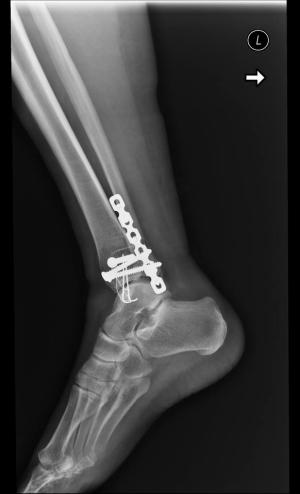

Były wzloty i upadki, z których starała się wszelkimi sposobami podnieść. Dawała jeszcze radę. Jednak w lutym 2016 r. doznała poważnego urazu nogi w wyniku wypadku. Przesiadła się na wózek inwalidzki. Dwie operacje i walka o nogę, żeby jej nie amputowali.